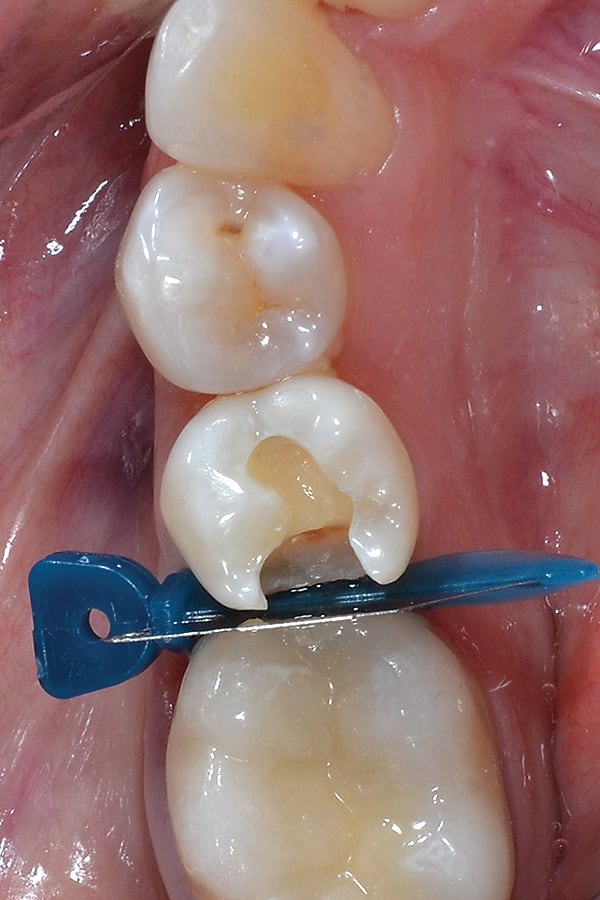

3. Rubber dam was placed and isolation of the preparation was achieved using the Palodent® Plus Sectional Matrix System (DENTSPLY Caulk), which consists of three parts: an EZ-Coat sectional matrix, a nickel-titanium ring, and Wave wedges. As shown, the system provides excellent isolation, and, because the ring facilitates tooth separation, contact creation is simple and predictable.